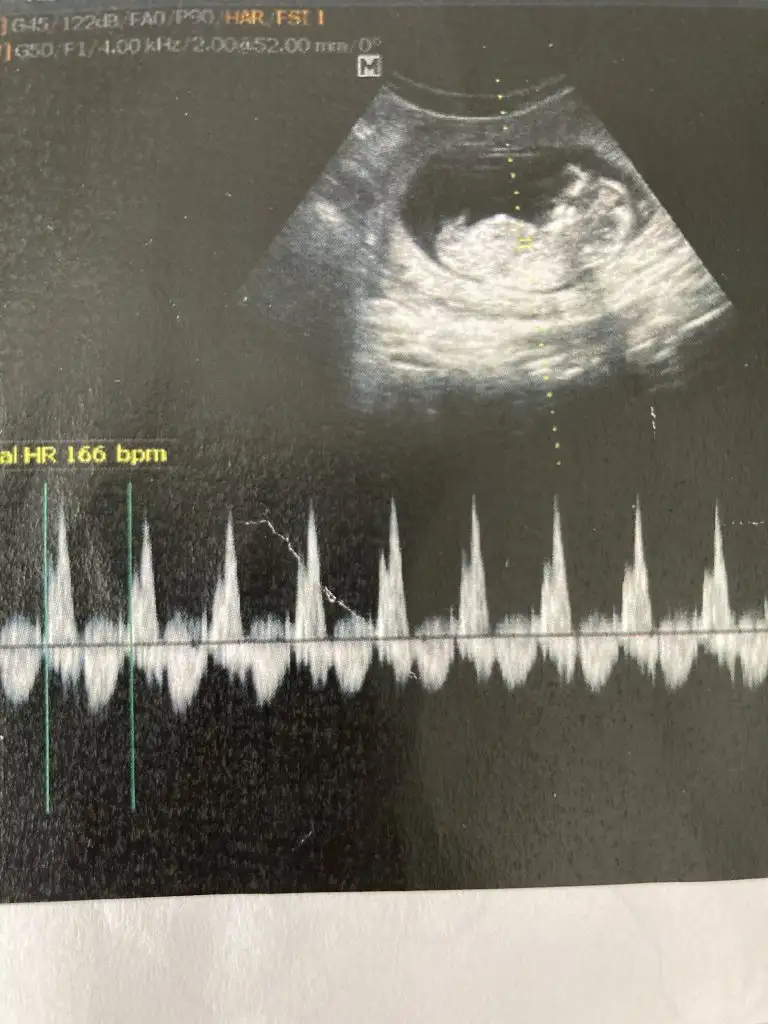

Canim yeni fotolarim geldi bakabilir misin bir Dr erkek dedi Kordon'da olabilir dedi..bugünde başka Dr gittim kıza benziyor dedi..kalp atışı olan fotoda solda bacakları nubu var yandan da baktı dr görebilmek için .sen ne düşünüyorsun

Eklentiler

• IMG20210427113328.webp

18,4 KB · Görüntüleme: 50

• IMG20210427113336.webp

11,2 KB · Görüntüleme: 55

Emin olmadım ama kız sanki önceki usgde kız demiştim